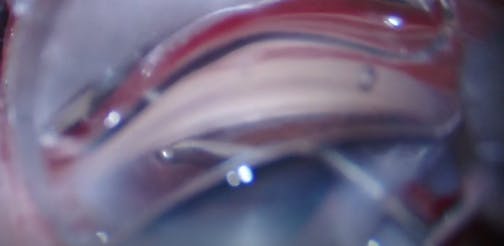

We describe a viscodilation of the Schlemm's canal using the iTrack device (Ellex) over 360 degrees followed by the implantation of two trabecular microbypass stents (iStent, Glaukos). At the end of the case, laminar flow through the aqueous veins help confirm the patency of the device. Presented by Georges Durr.